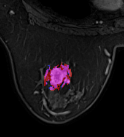

Detecting breast cancer on MRIs using deep learning (MRI classification and segmentation)